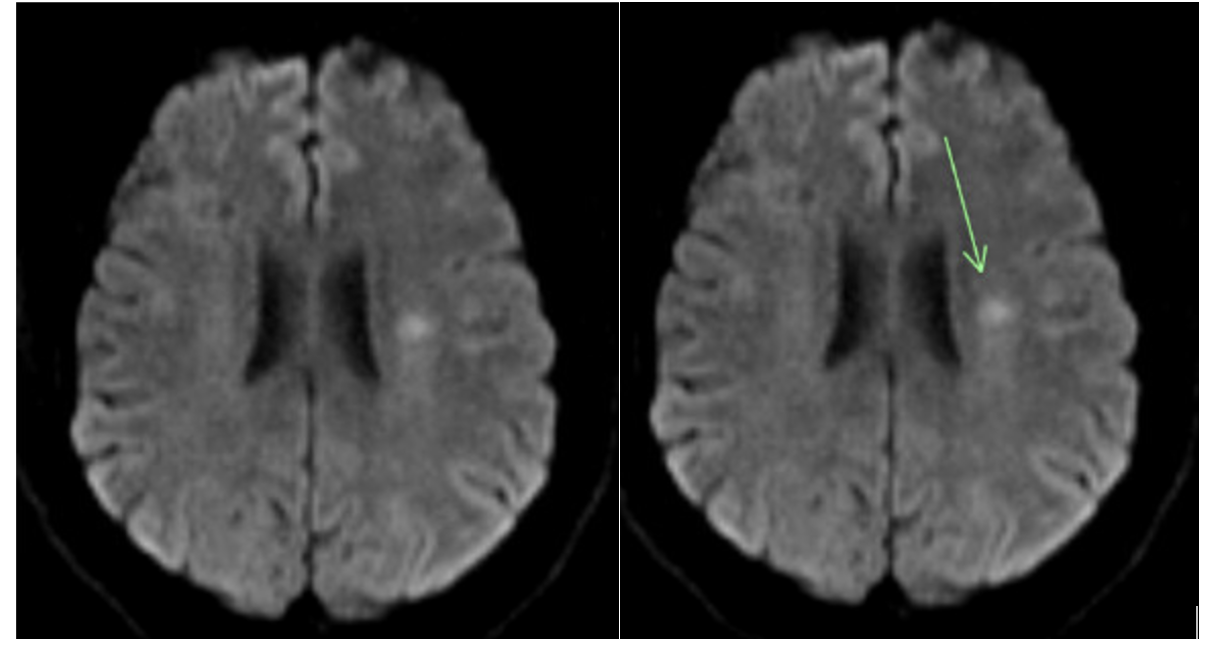

A 47-year-old woman with a history of well-controlled non-insulin-dependent diabetes mellitus and essential hypertension presented to the emergency department (ED) in 2015 complaining of right-sided facial, upper extremity, and lower extremity weakness with associated dysarthria. The patient was in her usual state of health until 1 hour before presentation. A computed tomography (CT) scan revealed ischemic stroke on the left side of the basal ganglia and posterior limb of the internal capsule. Magnetic resonance imaging (MRI) showed an acute infarction of the left motor cortex. The patient was given tissue plasminogen activator (tPA) and admitted. During admission, cardiac telemetry and transthoracic echocardiography were unrevealing. She was discharged on 81 mg of aspirin and 40 mg of atorvastatin 40 mg with cardiology follow-up. A loop recorder was implanted for 4 weeks and did not show evidence of atrial fibrillation. After 14 months, the patient returned complaining of 30 minutes of similar symptoms. MRI revealed an acute ischemic infarct in the left frontal corona radiata with chronic microvascular ischemic changes. The patient received tPA and fully recovered after 3 days of hospitalization. Telemetry was negative for atrial fibrillation and transesophageal echocardiography showed no evidence of left atrial appendage thrombus or patent foramen ovale. A digital subtraction angiography (DSA) was performed, which confirmed the presence of a small intimal web on the proximal cervical left internal carotid artery (Figure 1), but there was no evidence of significant cerebral stenosis or vasculitis.

Recurrence of cardiovascular accidents (CVA) occurs frequently. Studies have demonstrated recurrence of CVA in 26% of patients within 5 years.3 This case reports a patient on antiplatelet therapy with recurrent CVA with no identifiable cause. Her stroke was classified as cryptogenic due to a lack of evidence of etiology despite repeated tests to rule out cardioembolic, aortoembolic, or atheroembolic causes. Since all the strokes occurred within the region of the left internal carotid artery (Figures 2-4), we suspect they were caused by the left internal carotid web. During DSA, the neurosurgeon noted in the operative note that the extracranial left carotid artery circulation exhibited normal caliber and course, with the exception of a very small, eccentric intimal web at the junction of the left internal carotid artery bulb and proximal cervical segment. While most carotid webs are found in the carotid bulb’s posterior margin, the carotid web in this case appeared in the anterior and distal aspect. Theoretically, a carotid web could form anywhere along the carotid artery where a thin, membrane-like shelf of tissue that extends from the wall to the lumen exists. The multitude of infarcts in the left internal carotid’s territory helps to support that this patient has a carotid web rather than a kinked or tortuous vessel, and that it has a probable role in stroke etiology.